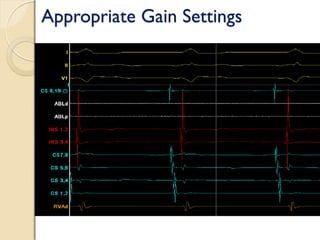

Signal Amplification

 Low gain - Surface ECG, Unipolar IC signals

 Moderate gain - RV, RA,CS signals

 High gain

◦ His signals (100-μV*)

◦ Mapping catheter signals

◦ Pulmonary vein catheter signals

 Issues include gaining up noise, saturation of current causing amplifier

to blank out (typically flat line) and display no signals

Appropriate Gain Settings